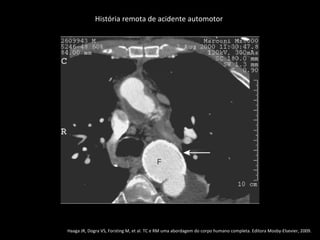

História remota de acidente automotor

Haaga JR, Dogra VS, Forsting M, et al. TC e RM uma abordagem do corpo humano completa. Editora Mosby-Elsevier, 2009.